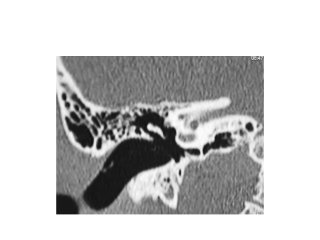

Right ear. Endoscopic anatomy of inferior retrotympanum. fu fustis, t tegmen, pp

posterior pillar, f finiculus, j jacobson’s nerve

Right ear. Endoscopic anatomy of the retrotympanum during

dissection for acustic neuroma surgery.

fu fustis, fn facial nerve, ow oval window, pr promontory, scc

subcochlear canaliculus, et Eustachian tube

Right ear. Endoscopic dissection during surgery, after drilling the

promontory. ow oval window, st scala tympani, scc subcochlear

canaliculus

Subcochlear canaliculus type A

Subcochlear canaliculus type B

Subcochlear canaliculus type C